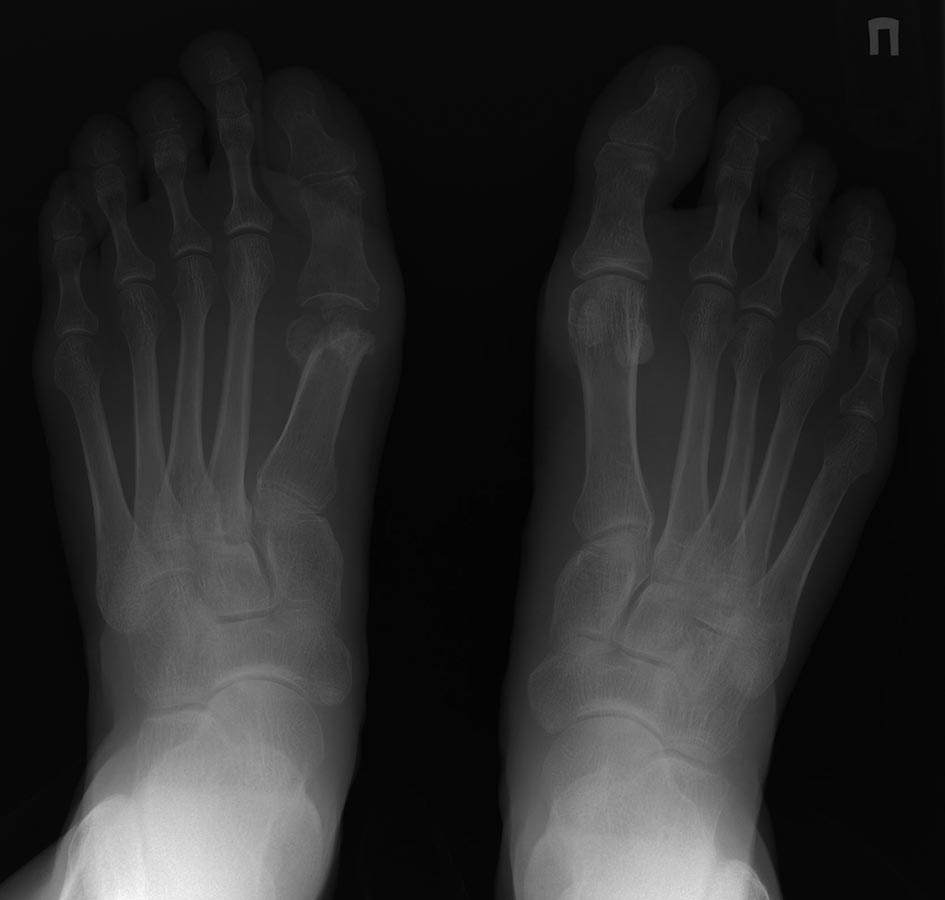

1.Удивительно,что еще где-то делается операция Вредена-Мейо. В 80-х иногда такие картинки видел,сейчас нет.

О как! Кривой Вреден! Наверное удлинняющую 1 пф кость остеотомия, по типу Скарф и попробовать протез 1 ПФС. КТ или МСКТ бы для начала.

Thank you for this interesting case, the patient looks to be Rhecumatoid and her function should be dependent on other joints function. If she would be 70, I would resect 2-5 MP joints. If her function is good, a fusion in the operated side, with trial of elongation is a good idea. A lot of surgery assuming she doesn't have infection. Good luck in this difficult case. Dr Liberson.

Если судить по второй стопе (длинная М1, нормальный М1М2 и отклонение 1-го пальца кнаружи по типу hallux valgus interphalangeus), речь изначально могла идти о hallux limitus (о подвижности первого пальца на оперированной и здоровой стопах мы не знаем) и вмешательство на М1 с целью устранения hallux valgus было не нужно. Достаточно было остеотомии основной фаланги. Возможно, остеотомия М1 была выполнена с целью ее укорочения? В этом случае цель достигнута с избытком. Конечно, стопы и до операции могли быть разными. Не очень понятна причина боли в области сустава большого пальца. За счет укорочения достигнута выраженная декомпрессия в суставе, признаков артроза нет, асептического некроза тоже нет. Почему болит?Может головка М1 "кивнула" вниз при остеотомии и срослась в положении подошвенного сгибания? Тогда артродез будет сложно выполнить и он не даст желаемого результата. И протез фиксировать в такой головке тоже крайне проблематично. Нужна рентгенограмма в боковой проекции. Еще лучше - КТ. Возможно, окажется необходима корригирующая реостеотомия М1. С латеральными лучами понятнее. Хотя, было бы неплохо узнать, есть ли натоптыши под головками М2-3. Фотографии стопы тоже не помешали бы.

Головки там не наблюдается. Я за артродез и удлиннение.

Многоуважаемый Сергей Бережной, боли возникают по причине отсутствия головки 1 плюсневой кости,вследствие чего возникает выраженная нагрузка на 2 и 3 плюснефаланговые суставы вследствие этого и возникают метатарзалгии в вышеуказанных областях. На мой взгляд нужно попробовать сделать артродез 1 плюснефалангового сустава(можно с небольшим аутотрансплантатом - во Вредена как то этим занимались вроде) и плюс Вейль на 2 и 3. Не судите строго за мнение.

Причина центральной метатарзалгии в данном случае очень понятна, так же как и то, что нужно делать по этому поводу: любые укорачивающие и поднимающие головки М2-3 (4?) остеотомии. Но автор поста написал о болях в суставе большого пальца. Для меня причина этой боли непонятна. Соответственно, и что делать по данному поводу неясно. Говорить, что у пациентки полностью отсутствует головка М1 мы не можем. Во вложении я обрисовал то, что точно осталось от головки.

Но в каком положении находится этот фрагмент и насколько он велик, и есть ли еще остатки головки, без рентгенограммы в боковой проекции или КТ я не знаю. Предположим, что будет выполнен артродез. Если для его выполнения резецировать остатки головки, то при таком большом расстоянии между М1 и основной фалангой, как сейчас, даже установка между артродезируемыми поверхностями трансплантата толщиной 1 см приведет к еще большему укорочению первого луча. Избавит ли такой артродез пациентку от болей? Очень сомневаюсь. Потому что не понимаю, чем анкилоз ПФС1 будет лучше представленного на снимках состояния. К сожалению, без дополнительной информации дальнейшее обсуждение данного случая потеряло смысл.